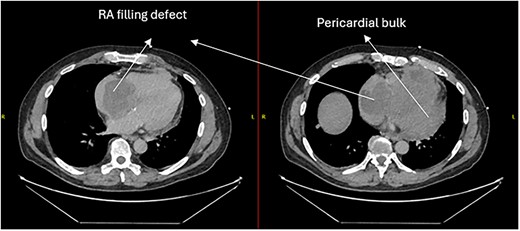

A 52-year-old gentleman was admitted to a district general hospital for shortness of breath causing type 1 respiratory failure with oxygen saturations of <90% despite high flow oxygen. His past medical history was unremarkable, and he was usually fit and well. A CT Pulmonary Angiogram (CTPA) was undertaken, which showed a heterogeneous oval-shaped lesion measuring 15 × 9 × 14 cm3 between the heart and the diaphragm, with a median attenuation of 35 HU and no enhancement during the arterial phase. Further solid lesions of 14 mm in the right lower lobe and 5 mm in the right upper lobe raised the suspicion of a primary cardiac sarcoma with pulmonary metastasis. This is shown in Fig. 1. Subsequent urgent CT staging (Fig. 2) was undertaken, which confirmed an indeterminate space occupying the inferior pericardial space, right atrial (RA) filling defect and anterior nodular pericardial thickening. No intra-abdominal or bone lesions were identified. An echocardiogram also confirmed these finding with the addition of no flow through the tricuspid valve (TV), as shown in Fig. 3.

CT thorax-abdomen pelvis, depicting the RA filling defect as well as pericardial bulk.